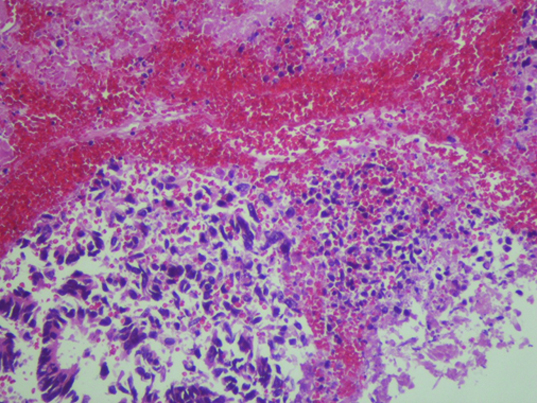

Percutaneous transhepatic cholangiography was then performed after ciprofloxacin prophylaxis. Internal-external drainage was placed during the intervention. During the procedure, solid material occupying the bile duct was unexpectedly identified [Table/Fig-1]. Pathological analysis demonstrated the presence of solid tumour fragments of adenocarcinoma [Table/Fig-2]. At this time, microbiological study of biliary fluid did not detect bacterial cholangitis. Given these findings, abdominal CT images were reviewed which revealed increased iodinated contrast uptake within the dilated bile duct, suggestive of bile duct tumour invasion [Table/Fig-3].

Histologic findings of the isolated biliary drainage solid fragments (HE stain). The histologic features were indicative of an adenocarcinoma. The liver and intrabile duct tumours resembled the colon carcinoma.